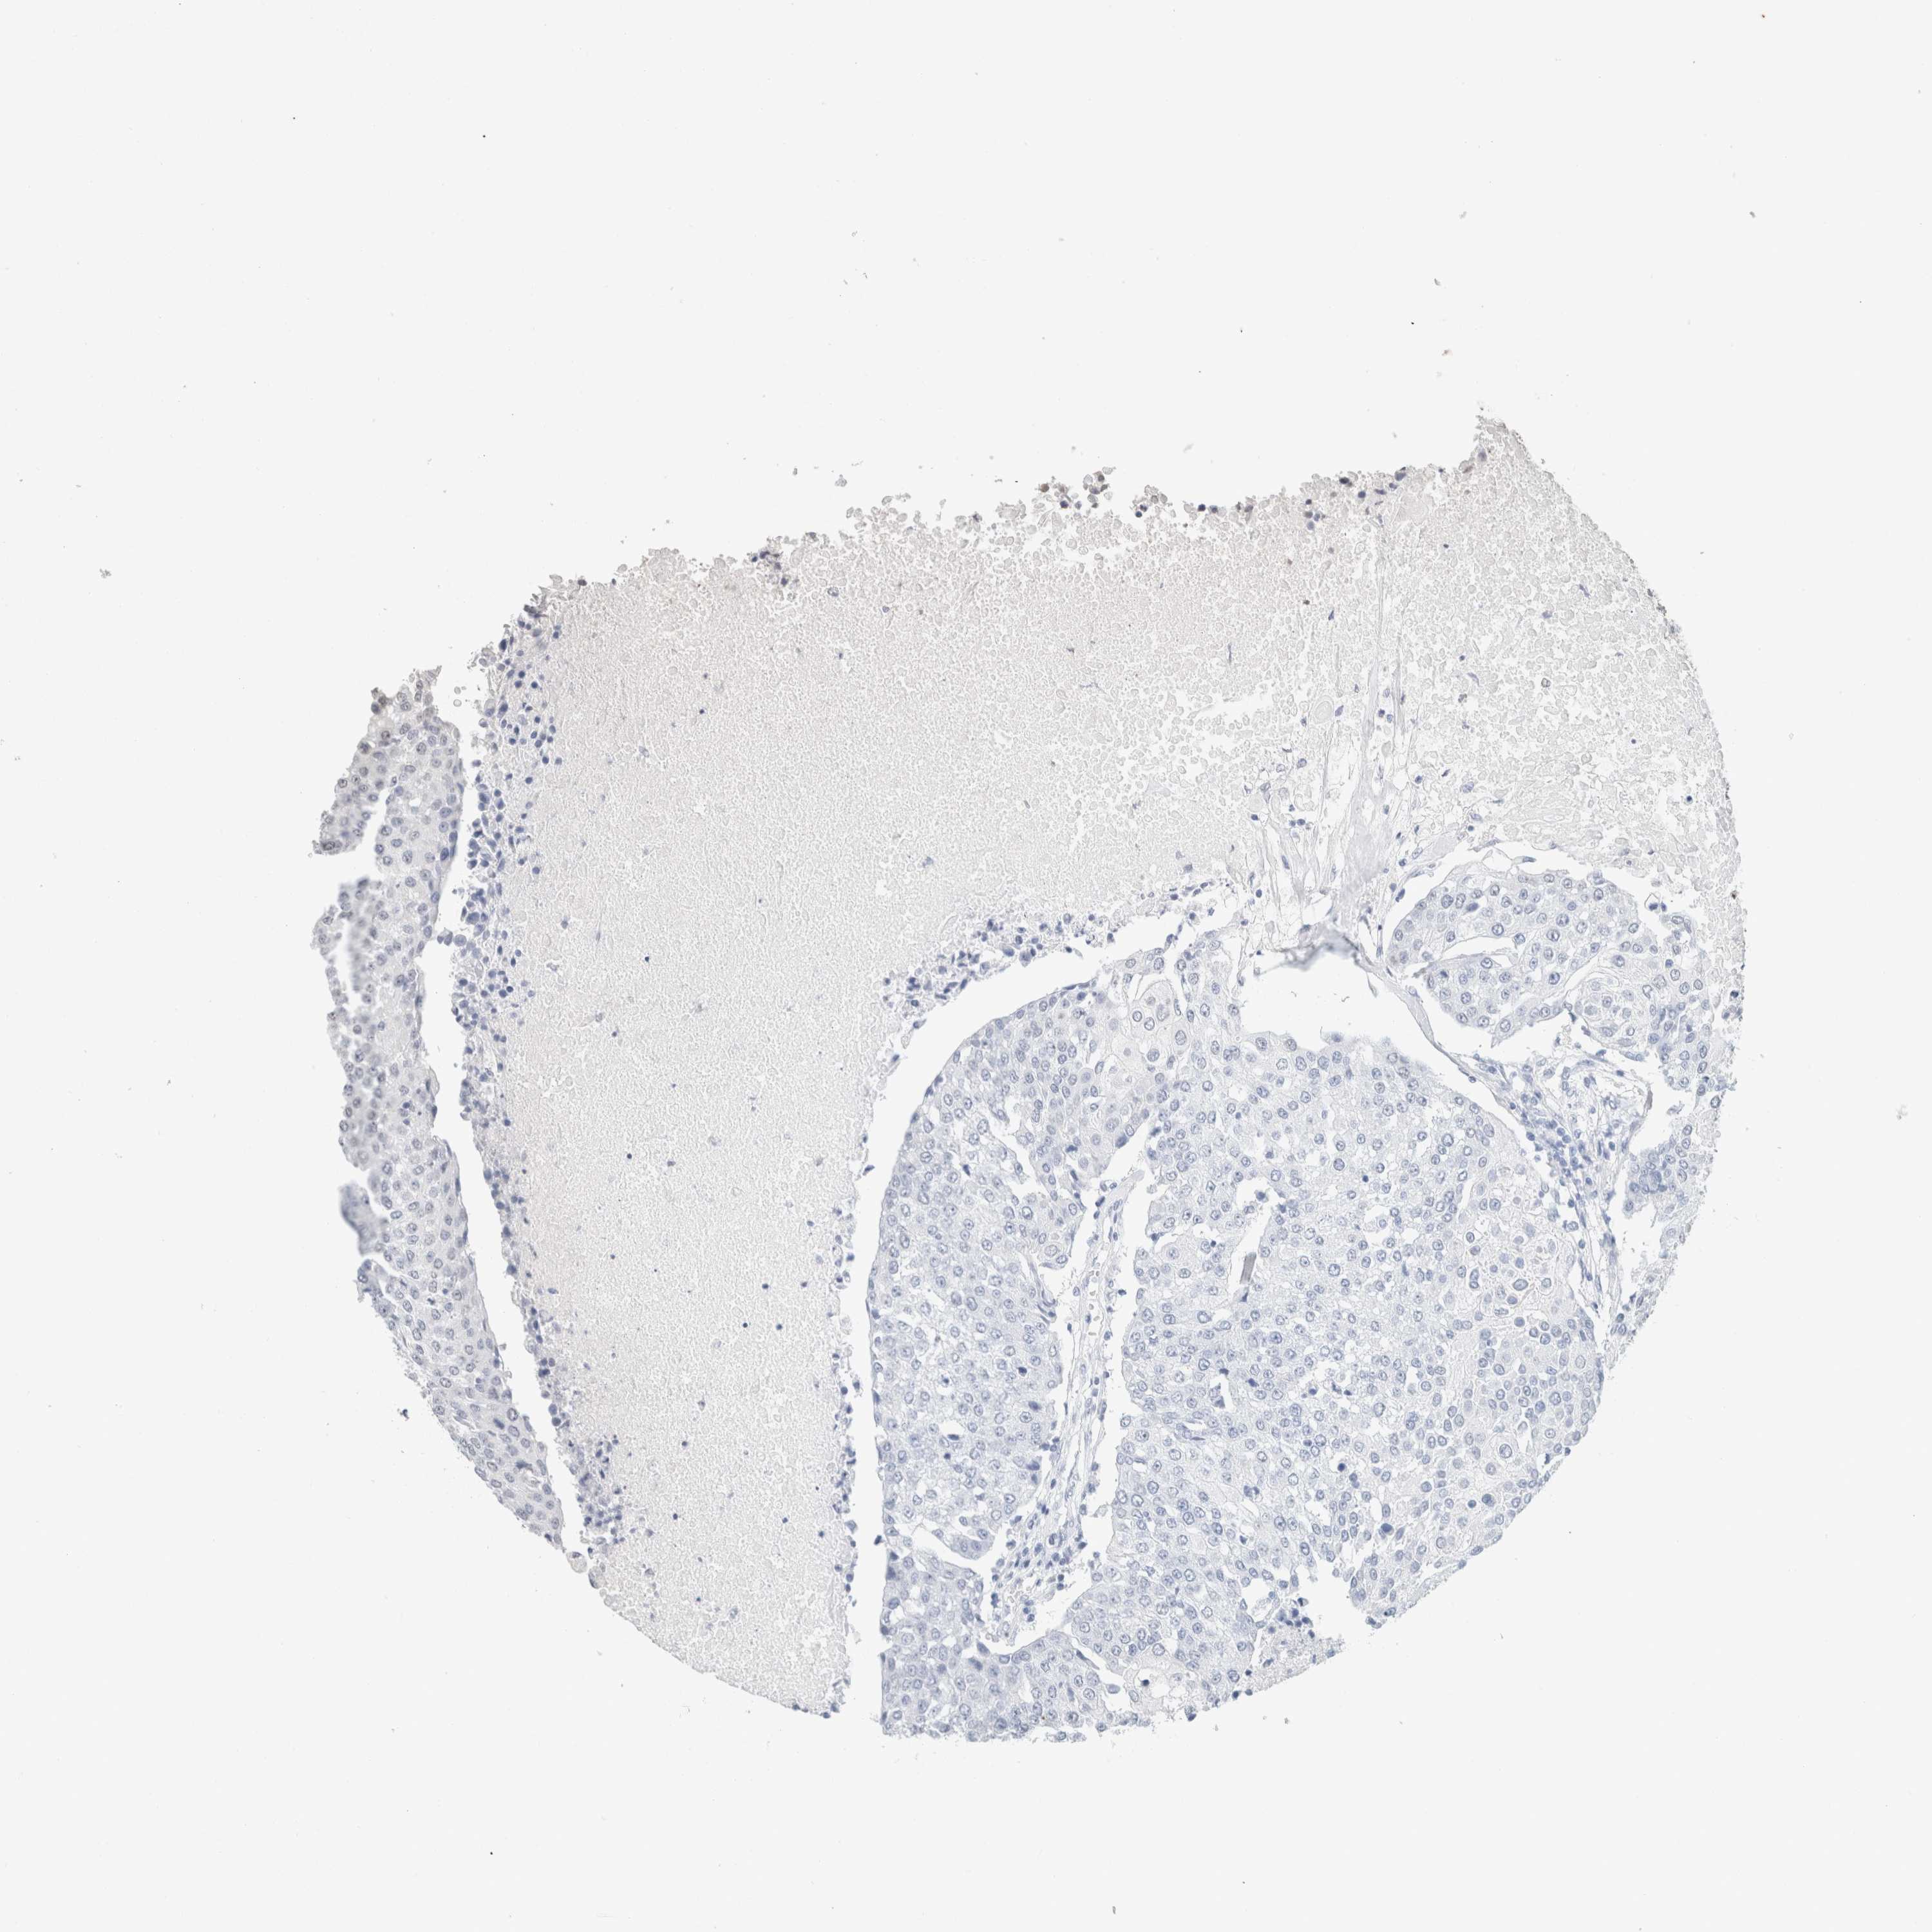

UROTHELIAL CANCER - Protein expressioni

A mouse-over function shows sample information and annotation data. Click on an image to view it in a full screen mode. Samples can be filtered based on level of antibody staining by selecting one or several of the following categories: high, medium, low and not detected. The assay and annotation is described here.

Antibody stainingi

Antibody staining in the annotated cell types in the current human tissue is reported as not detected, low, medium, or high, based on conventional immunohistochemistry profiling in selected tissues. This score is based on the combination of the staining intensity and fraction of stained cells.

Each image is clickable and will lead to virtual microscopy that enables deeper exploration of all samples and also displays staining intensity scores, fraction scores and subcellular localization as well as patient and tissue information for each sample.

Antibody HPA050092

Antibody CAB025368

Urothelial carcinoma, High grade

Urothelial carcinoma, Low grade